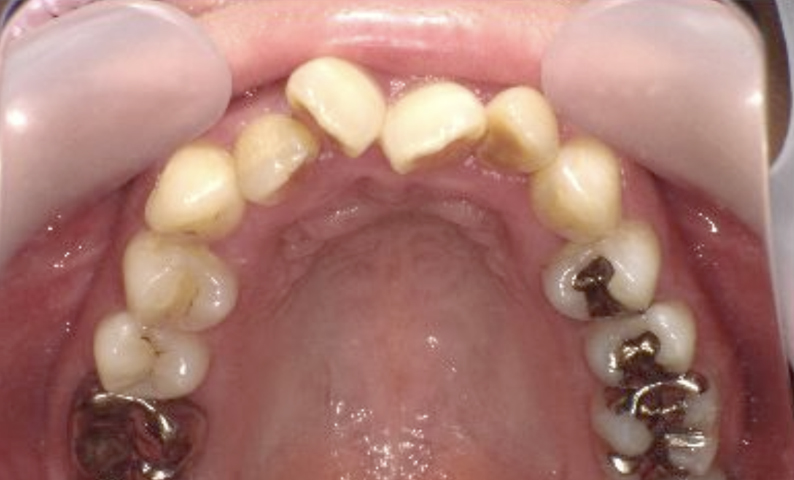

症例_008 上顎だけの部分矯正

治療期間:9ヶ月金額:24万円+税女性前歯のガタガタ上の前歯だけ

| Before | After |

|---|---|

|